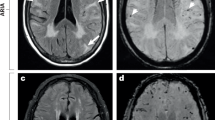

The aggregation of Aβ in the brain is a major neuropathologic hallmark of AD, but whether Aβ deposits in peripheral immune organs such as the bone marrow remains unknown in patients with AD. For this purpose, Aβ accumulation was assessed via the regional cortical tracer uptake (RCTU) system by positron emission tomography/computed tomography (PET/CT).35,36 A total of 26 dementia patients were included, comprising 8 non-AD dementia patients with negative brain Aβ-PET scans and 18 AD dementia patients with positive brain Aβ-PET scans (supplementary Table 1). In addition to Aβ deposition in the brain parenchyma, Aβ accumulation in the skull bones and other peripheral bones was detected in patients with AD dementia compared with non-AD dementia patients (Fig. 1a). Analysis of tracer uptake revealed that the standardized uptake value ratio (SUVr) in the skull of patients with AD dementia was markedly greater than that in non-AD dementia patients (Fig. 1b). Interestingly, Aβ deposits were also found in the bone marrow of flat bones, such as the ilium, in AD dementia patients but not in the bone marrow of long bones (e.g., the femur) in any patient group. When SUV values in skull subregions were analyzed according to corresponding cerebral cortex regions, significant increases were found in the frontal, temporal, and occipital skulls of patients with AD dementia compared with those with non-AD dementia, whereas the parietal skull showed no significant difference (Fig. 1c). These results demonstrate that Aβ is deposited within the skull bone marrow of AD dementia patients.

Aβ accumulates in the skull BM of patients with AD and AD model mice. a 18F-92 and 18F-AV45 PET/CT scanning analysis of Aβ deposition in the brain and bone marrow. Images demonstrating the uptake of the PET tracers in the body bone marrow of the non-AD dementia group and AD dementia group. The white arrows indicate the cranial parietal spine, lumbar spine, iliac crest and femur. b, c Quantitative measurement standardized uptake values of the skull, ilium, lumbar, and femur (b) and subregions of the skull (c) (SUVr). n = 8 and 18 skulls and subregions of the skull for non-AD dementia patients and AD dementia patients, respectively. n = 4 and 12 ilium, lumbar, and femur for non-AD dementias and AD dementias patients, respectively. d, e Hypersensitive ELISA analysis of Aβ42 in the supernatant of skull and femur bone marrow from 5 × FAD mice (d), APP/PS1 mice (e) and littermates of WT counterparts. n = 6–8 mice per group. f Immunohistochemical staining showing Aβ deposition in the skull bone marrow of 5-month-old WT (top) and 5 × FAD (bottom) mice. The data are expressed as the means ± SEMs. *p < 0.05, **p < 0.01; two-tailed unpaired Student’s t test was used